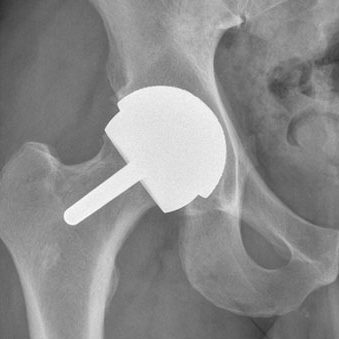

O mundo da ortopedia prepara-se para mais uma edição do 3.º HIP G.I.N. (Global Issue Network) Summit, um evento dedicado às grandes questões da cirurgia da anca. Organizado pelo Lusíadas Knowledge Center em parceria com a UpHill Events, o summit ocorrerá nos dias 21 e 22 de novembro de 2025, na Herdade da Comporta, reunindo…